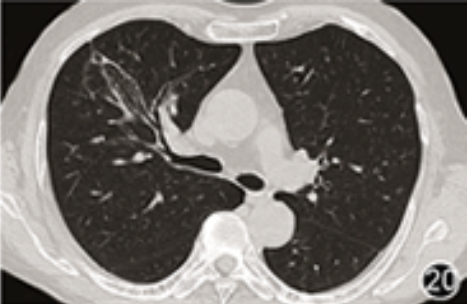

患者男,60岁,因“干咳伴咳嗽时胸闷1个月”于2018年5月入院。患者1个月前无明显诱因出现干咳,伴咳嗽时轻微的胸闷。13 d前患者在外院的胸部CT提示右上肺外周斑片影(图1、2),被诊断为社区获得性肺炎,经1周的左氧氟沙星(0.5 g,1次/d)口服治疗,症状未见缓解。1 d前来我院,查外周血嗜酸粒细胞计数升高(表1),胸部CT提示病灶较前增大(图3),且伴有右上肺前段内侧支(RB3b)支气管明显的堵塞(图4),遂收入院。既往体健。5个月前曾因摔伤致右肱骨外科颈骨折在我院手术,当时胸部CT及血嗜酸粒细胞计数正常。否认支气管哮喘及其他重大疾病史。偶有吸烟、饮酒。

图1 2018年5月2日外院胸部CT(肺窗):右上前段内侧支斑片实变影

图2 2018年5月2日外院胸部CT(肺窗):右上前段内侧支斑片实变影其相应支气管(RB3b)堵塞,指套征

图3 2018年5月14日胸部CT(肺窗):右上前段内侧支实变影较前增大

图4 2018年5月14日胸部CT(肺窗):右上前段内侧支实变影其相应支气管(RB3b)堵塞